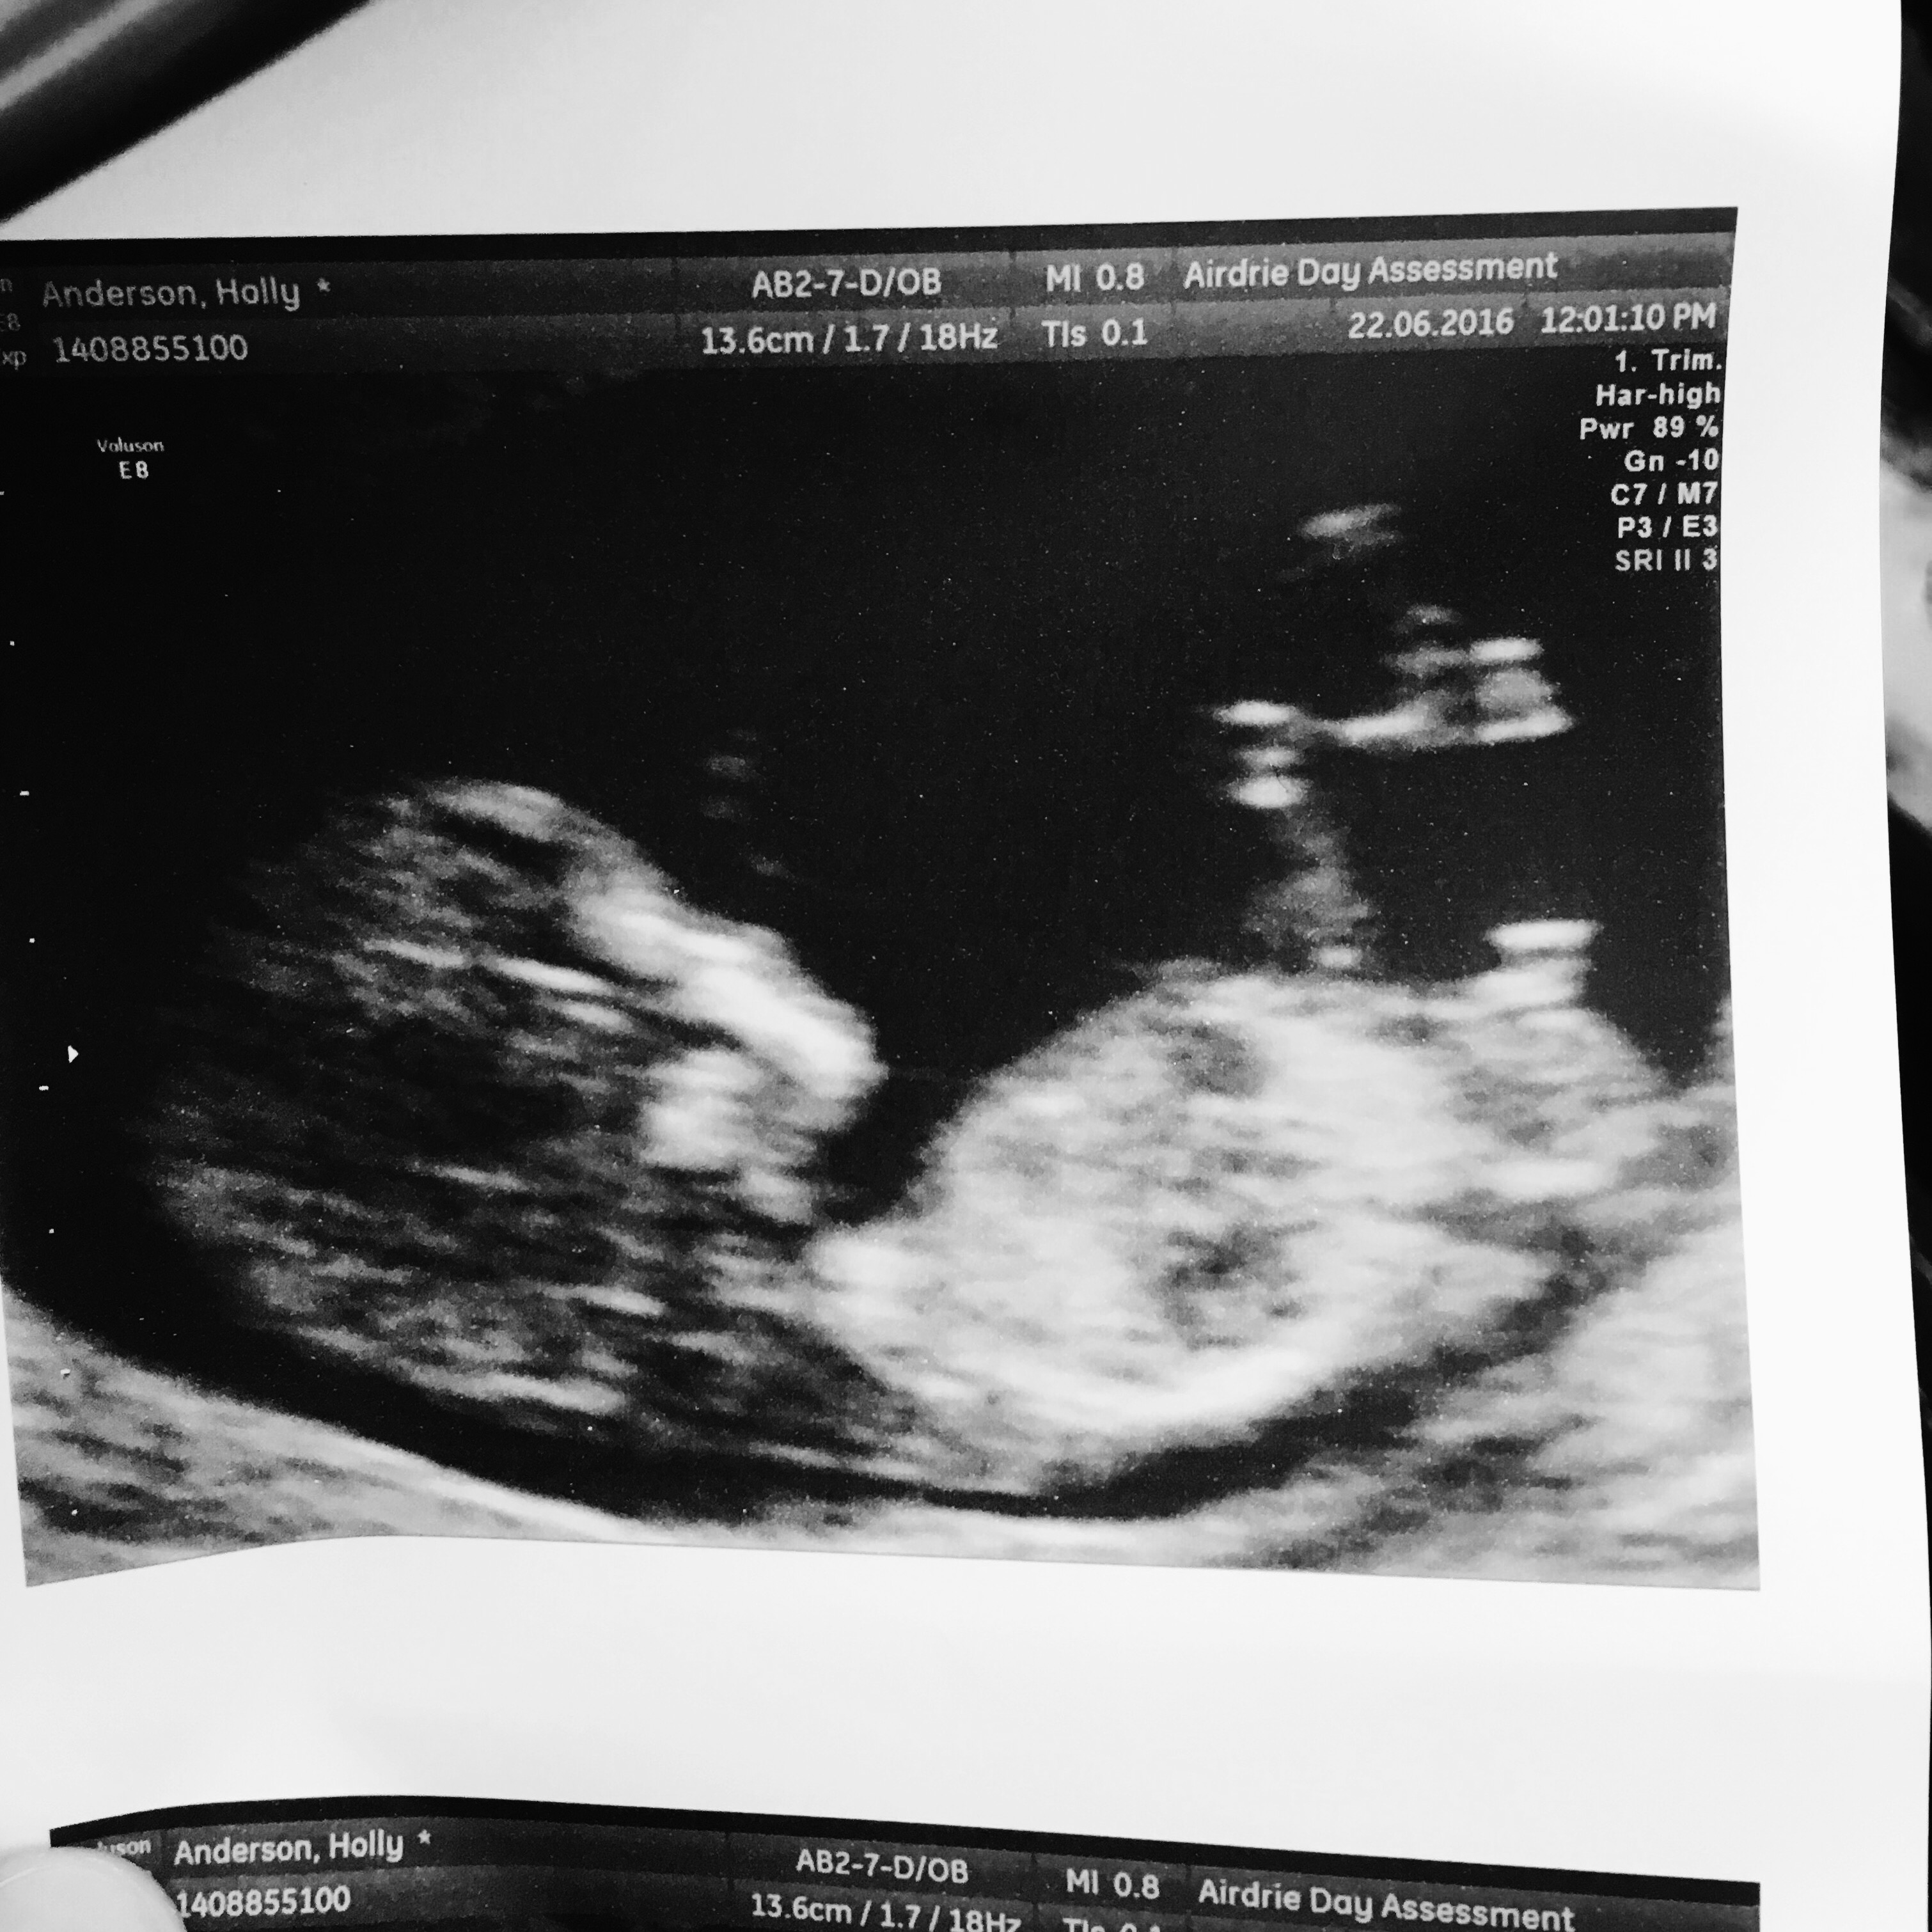

Attachment 31901

Does this look like a boy nub @ 11+6?

Thanks

Very early but it looks very boyish.

Very early, but I agree it looks boysh

The stacked nub in first pic makes me think boy. Sometimes a boy nub can image as a girl nub if only part of it is captured, which may be why it isn't captured in the other nub pic. But I hope you get your heart's desire.

First picture has the cord going past the nub so the part on top might be that or maybe stacking. I'm not100% sure